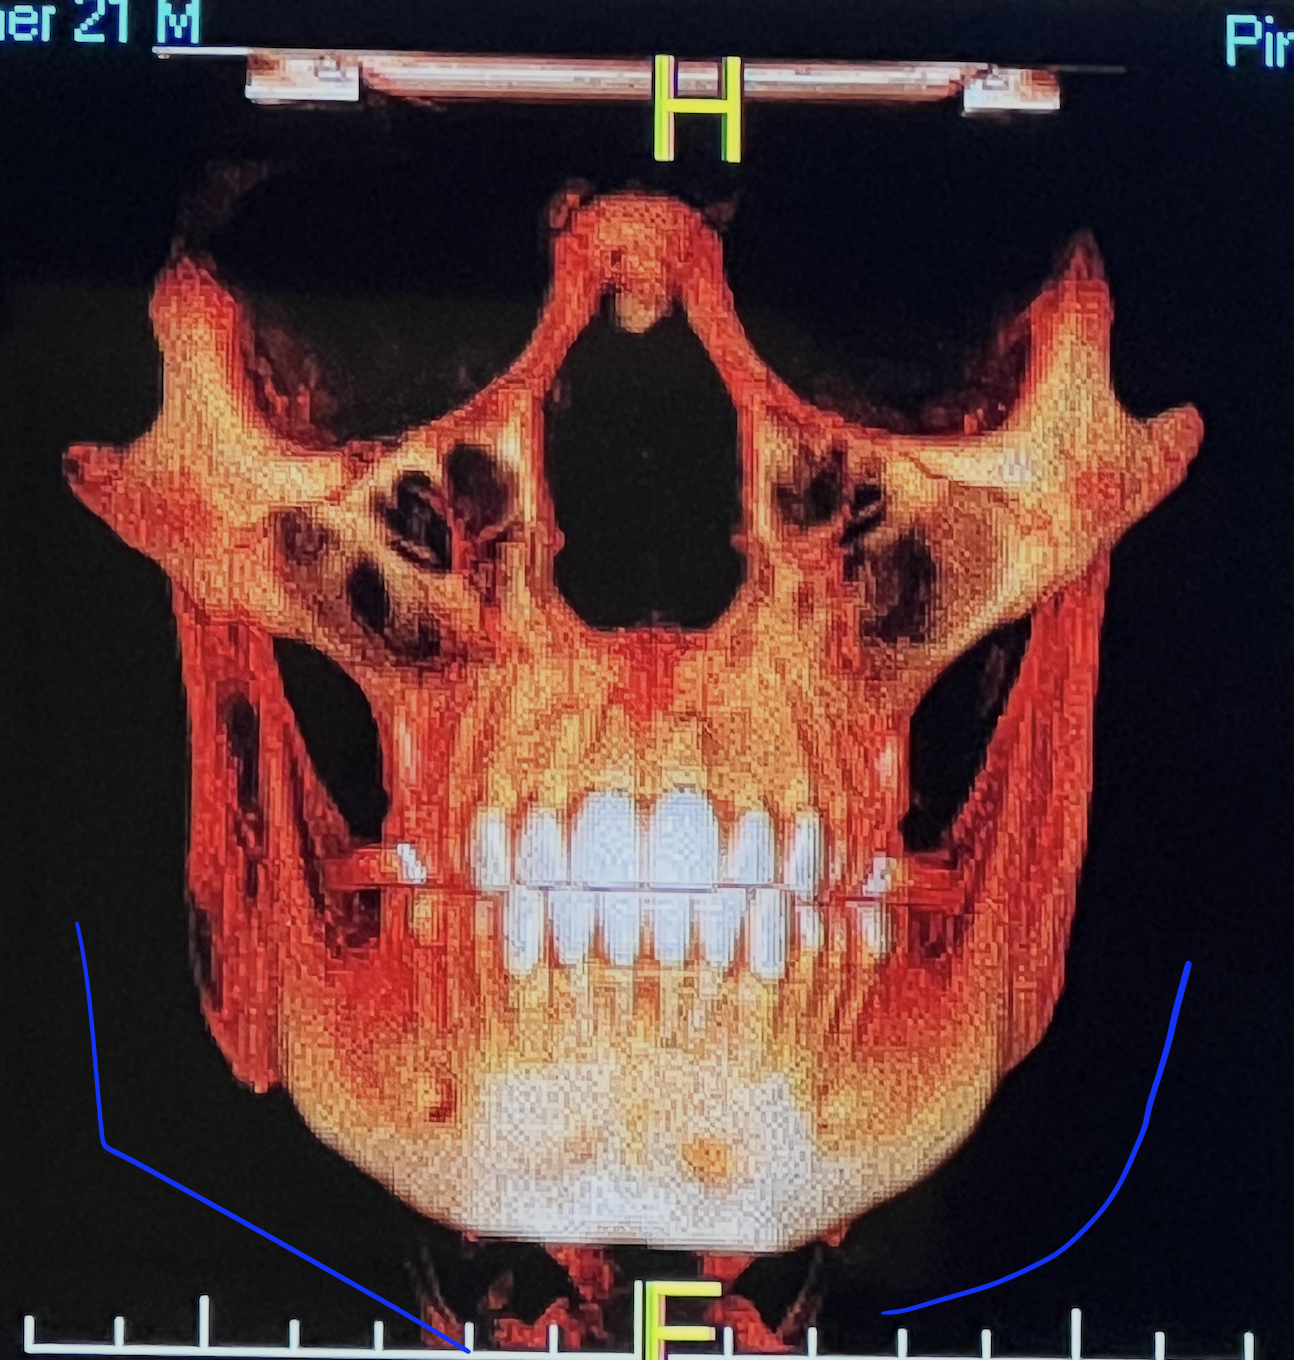

CBCT RENDERS

All attached. Frontal bone, left lateral, right lateral, soft tissue overlays, volume renders at different thresholds. The full skull, nothing hidden, nothing frauded with angles. You can see every problem I just described for yourself.

Is the trimax the correct priority or would you allocate differently? Are the zygo implants a must or does the LeFort do enough? Is there something in these renders, ramus, orbital rims, any structure, that I haven't accounted for? If you had my bones and my budget, what would the plan look like?

CBCT RENDERS

All attached. Frontal bone, left lateral, right lateral, soft tissue overlays, volume renders at different thresholds. The full skull, nothing hidden, nothing frauded with angles. You can see every problem I just described for yourself.

Is the trimax the correct priority or would you allocate differently? Are the zygo implants a must or does the LeFort do enough? Is there something in these renders, ramus, orbital rims, any structure, that I haven't accounted for? If you had my bones and my budget, what would the plan look like?